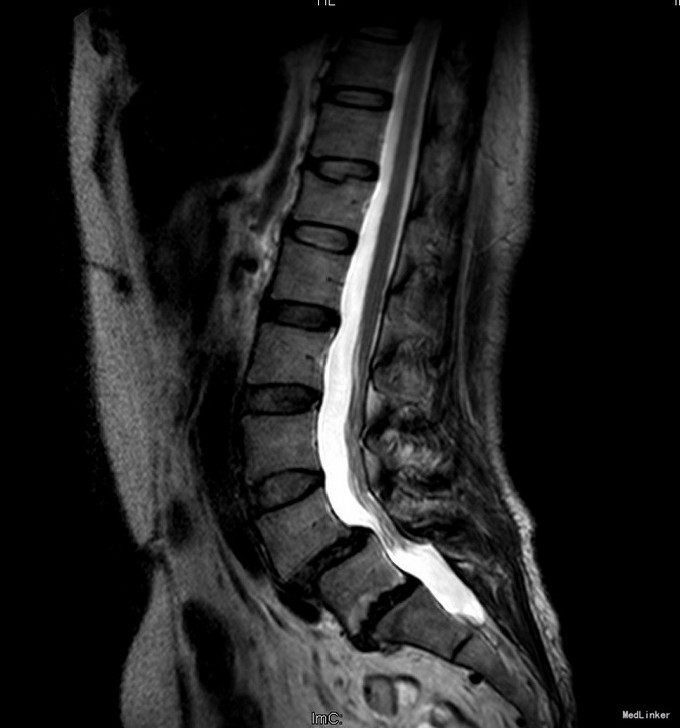

主诉:反复腰部疼痛20+年,加重伴双下肢胀痛麻木 现病史:患者于20+年前,因车祸行腰椎检查发现腰4椎体I°滑脱,并感腰部阵发性隐痛不适,一直未行特殊处理、4月前患者感腰部疼痛有所加重,并感双下肢阵发性胀痛麻木,久坐或弯腰后症状加重,以左下肢为甚,症状明显时难以直立行走,不伴畏寒发热、潮热盗汗等不适。10+天前患者在院外行理疗(具体不详),上述症状略有好转。在院外行腰椎x光摄片诊断为"腰4椎体II°滑脱,腰5椎体I°滑脱",故来我院就诊,门诊以"腰椎滑脱"收入住院

查体:脊柱外观无侧弯后突畸形,双下肢无肌肉萎缩。腰4-5、腰5骶1棘上棘旁轻压痛,伴左侧下肢放射;会阴部感觉未见异常,双侧小腿前外侧及足背足底感觉减退。腰椎前屈后伸及侧屈活动度正常;双下肢髂腰肌肌力4级,左侧直腿抬高试验阳性,加强试验阳性,左侧膝腱反射减弱,双侧病理征未引出。 辅助检查:院外腰椎正侧位片:腰4椎体II°滑脱,腰5椎体I°滑脱。

诊断:腰4椎II°滑脱症,腰5椎I°滑脱症 治疗:经后路腰4、5椎切开复位、椎管减压、Capstone椎间及后外侧人工骨+自体骨植骨融合、Legacy内固定术